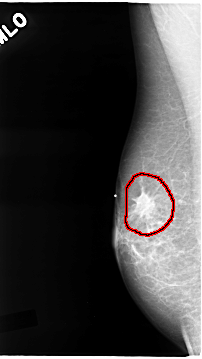

C_0069_1.RIGHT_MLO

RIGHT_MLO LINES 4664 PIXELS_PER_LINE 2616 BITS_PER_PIXEL 12 RESOLUTION 50 OVERLAY

FILE: C_0069_1.RIGHT_MLO.OVERLAY

TOTAL_ABNORMALITIES 1

ABNORMALITY 1

LESION_TYPE MASS SHAPE IRREGULAR MARGINS SPICULATED

ASSESSMENT 5

SUBTLETY 5

PATHOLOGY MALIGNANT

TOTAL_OUTLINES 1

BOUNDARY